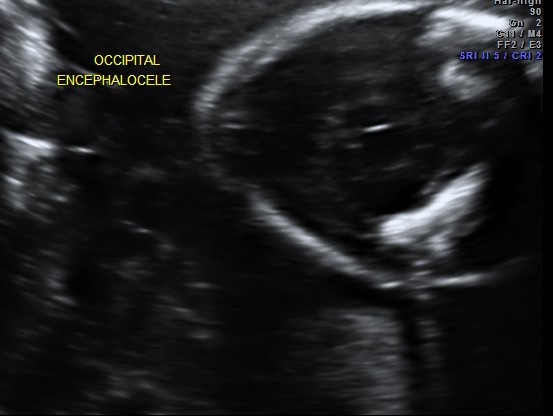

occipital encephalocele